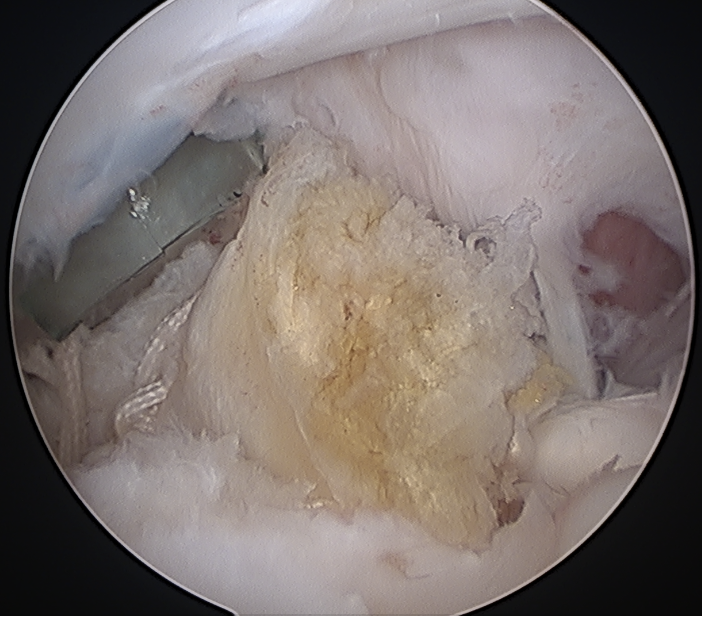

Tendonopathy

Medial subluxation of LHB